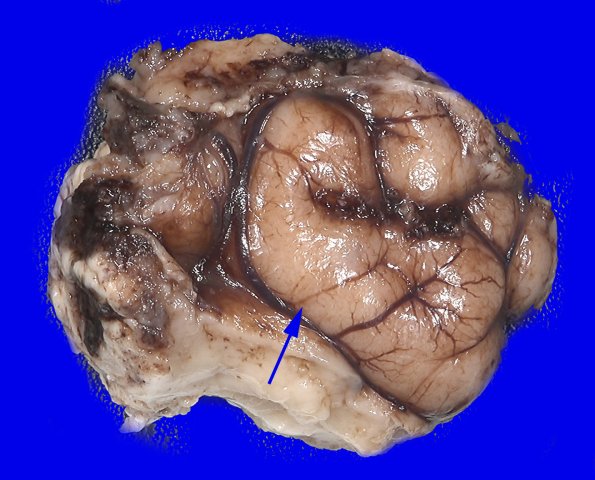

On cross section the tuber shows loss of grey white distinction (arrowhead) compared to other cortical areas of the specimen.